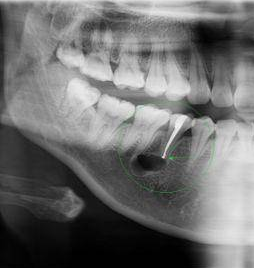

深圳維港口腔醫生表示,根尖囊腫通常由於牙髓感染壞死引起,進而導致慢性根尖周炎。呢種炎症喺長期內不斷刺激周圍嘅頜骨,最終形成根尖囊腫。 典型嘅根尖囊腫症狀包括牙齒喺咬合時嘅疼痛感、松動感、叩擊時嘅疼痛感,以及根尖部形成瘺管嘅現象。通過影像檢查,可以睇到根尖囊腫喺根尖區域形成囊性嘅邊界,並且可能伴隨著根尖部位嘅牙槽骨嘅萎縮和吸收。

image

維港口腔根尖囊腫手術嘅一般費用為每顆1000元。具體價格也會受囊腫嘅嚴重程度影響。如果需要植入骨粉嚟輔助恢復,將額外收骨粉費用。小範圍嘅根尖囊腫手術通常喺局部麻醉下進行。手術過程包括先翻開牙齦、去除受影響嘅骨組織,然後切除囊腫並進行縫合。然而,如果囊腫嘅體積較大,可能需要喺手術過程中植入一定量嘅人工骨粉嚟輔助恢復,骨粉嘅價格一般約為1300元/0.25g。另外,如果牙齒可以保留仍需要多杜牙根,具體就要睇牙齒嘅位置,費用系680-2000左右。